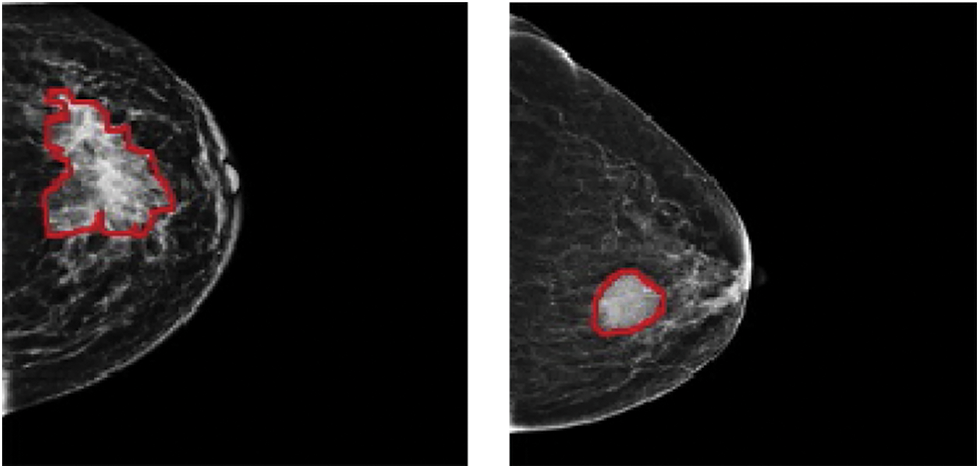

In 2020, 2.3 million women were diagnosed with breast cancer, with 68,500 worldwide fatalities. As of 2020, 7.8 million women have been diagnosed with breast cancer in the past five years, making it the world’s most prevalent cancer [1]. In clinical terms, malignant tumours are typically classified as positive, whereas benign tumours are classified as negative. Both cancers have subgroups that must be identified separately since each might have a different prognosis and treatment plan. Accurate identification of each subcategory is required for proper diagnosis. Mammography, ultrasound, magnetic resonance imaging (MRI), computed tomography (CT), positron-emission tomography (PET), and microwave imaging are now used in the diagnosis of breast cancer [2–7]. There are two types of breast cancer manifestations in medical images: masses and calcifications. On appearance, benign tumours are often spherical, smooth, and transparent. Calcification has a coarser form, a granular shape, a popcorn shape, or a ring shape, and it has a greater density and a more scattered dispersion. The margins of typical malignant tumours are uneven and typically fuzzy, and the mass has a needle-like appearance. Calcification has a morphology that is generally sand-like, linear, or branching, with various forms and sizes. The distribution is usually dense or clustered in a linear pattern [8–10]. Fig. 1 shows a picture of malignant and benign breast cancer.

Figure 1: (Left) Malignant and (Right) benign breast cancer images